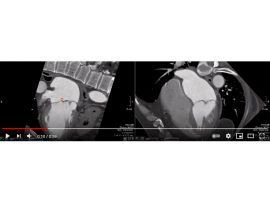

Tricuspid atresia , pulmonary atresia intact IVS Ductus dependent pulmonary circulation LMCA aneurysm Mohamed Gibreel , FEBR (Fellowship of Egyptian Board of Radiology ) Cardiac..